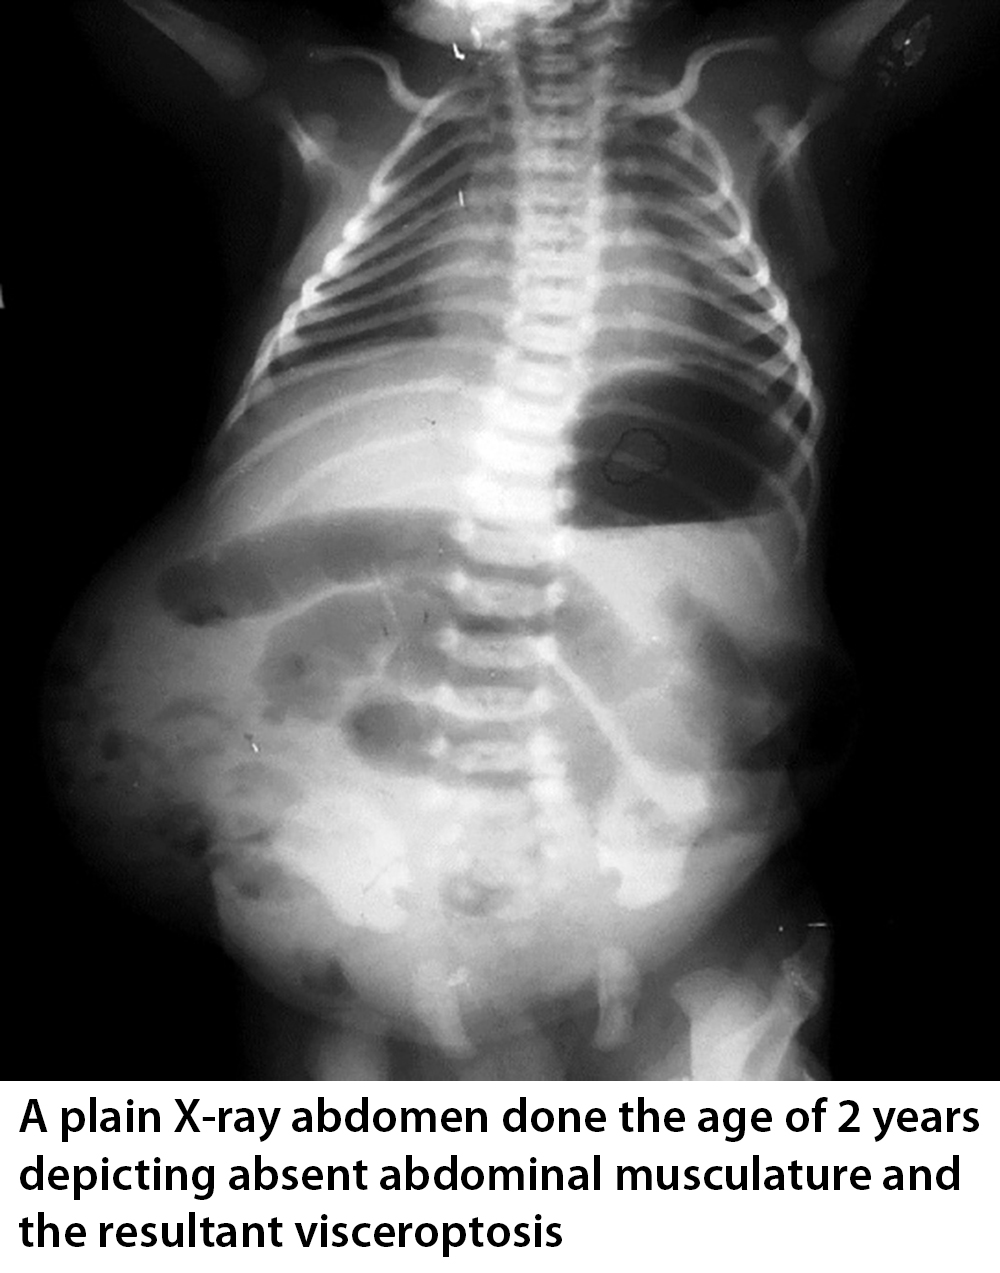

A lack of abdominal muscles leads to a poor cough mechanism, leading to increased pulmonary secretions. Weak abdominal muscles also lead to constipation because they cannot perform the Valsalva maneuver, which helps push the stool out of the rectum during defecation.

Kidney, ureter, and bladder (KUB) test findings can usually be used for diagnosis based on the typical appearance of the bowels hanging over the lateral edge of the abdominal wall. Enlarged bladder